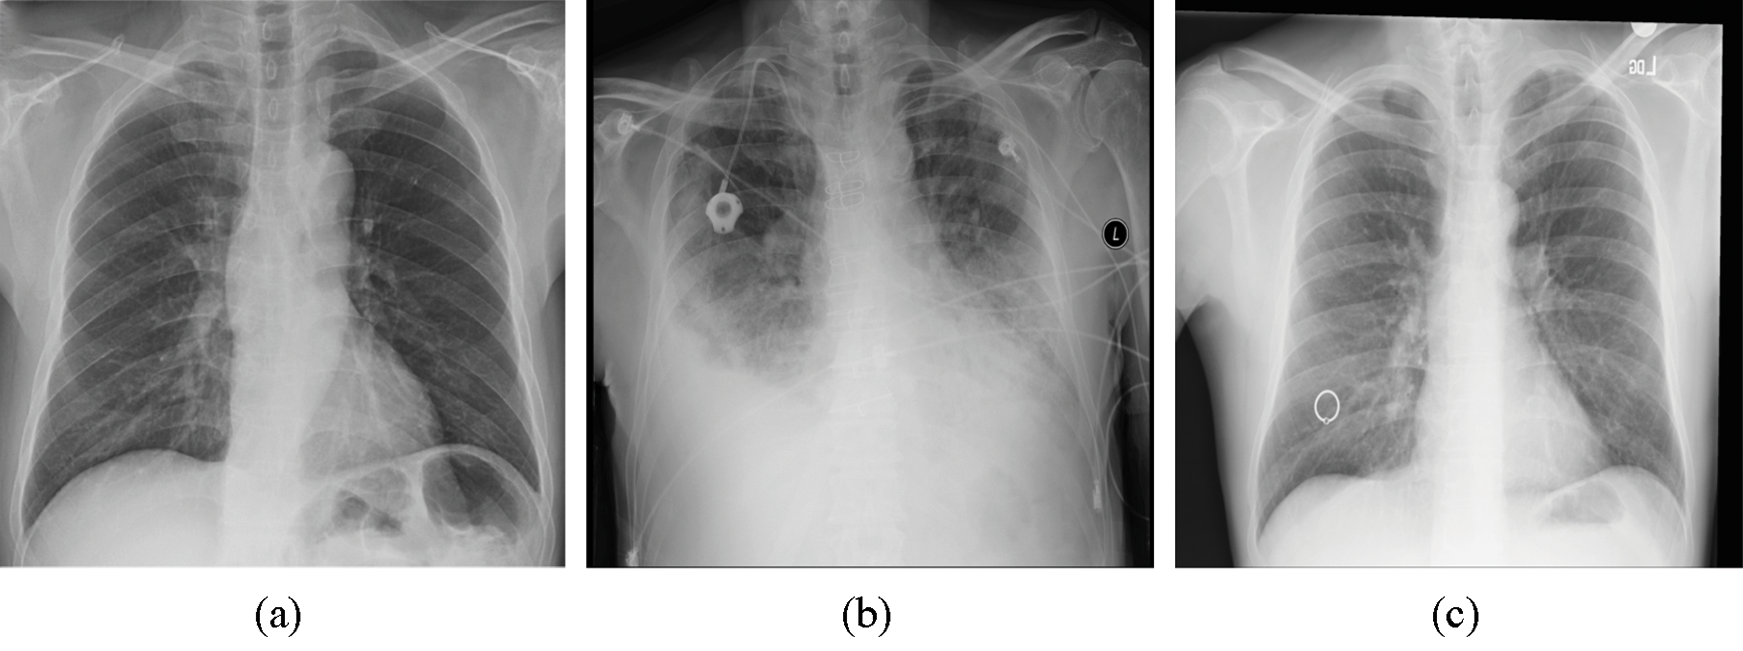

To evaluate the proposed method, we utilized the Python programming language. Two Python libraries designed for developing machine learning models, namely, Keras [33] and TensorFlow [34], were used to train the model and validate the results. The proposed model was trained by employing a collaborative environment that provides access to graphics processing units (GPUs) and tensor processing units (TPUs) (i.e., Google colaboratory (Colab)). A dataset provided by Ozturk et al. [32] was used to validate the proposed method. This dataset, which contains chest X-ray images, is designated for the early diagnosis of COVID-19. The X-ray images were collected from two different sources. The first set of X-ray images was collected by Cohen et al. [35] using images from various open access sources. The number of female COVID-19-positive cases is 43, while the number of male COVID-19-positive cases is 82. The average age of only 26 positive cases is 55 years. Some of the X-ray images samples present in this dataset are shown in Fig. 1. The other dataset was published by Wang et al. [36] for classifying common thorax diseases. The total number of samples collected from the two sources was 1,125 X-ray images. These samples belong to three classes: the first class, i.e., COVID-19, consists of 125 X-ray images, the second class, i.e., pneumonia, consists of 500 X-ray images, and the third class, i.e., the no-findings class, consists of 500 X-ray images.

Figure 1: Three images present in the dataset representing three classes: (a) COVID-19, (b) pneumonia, and (c) no-findings